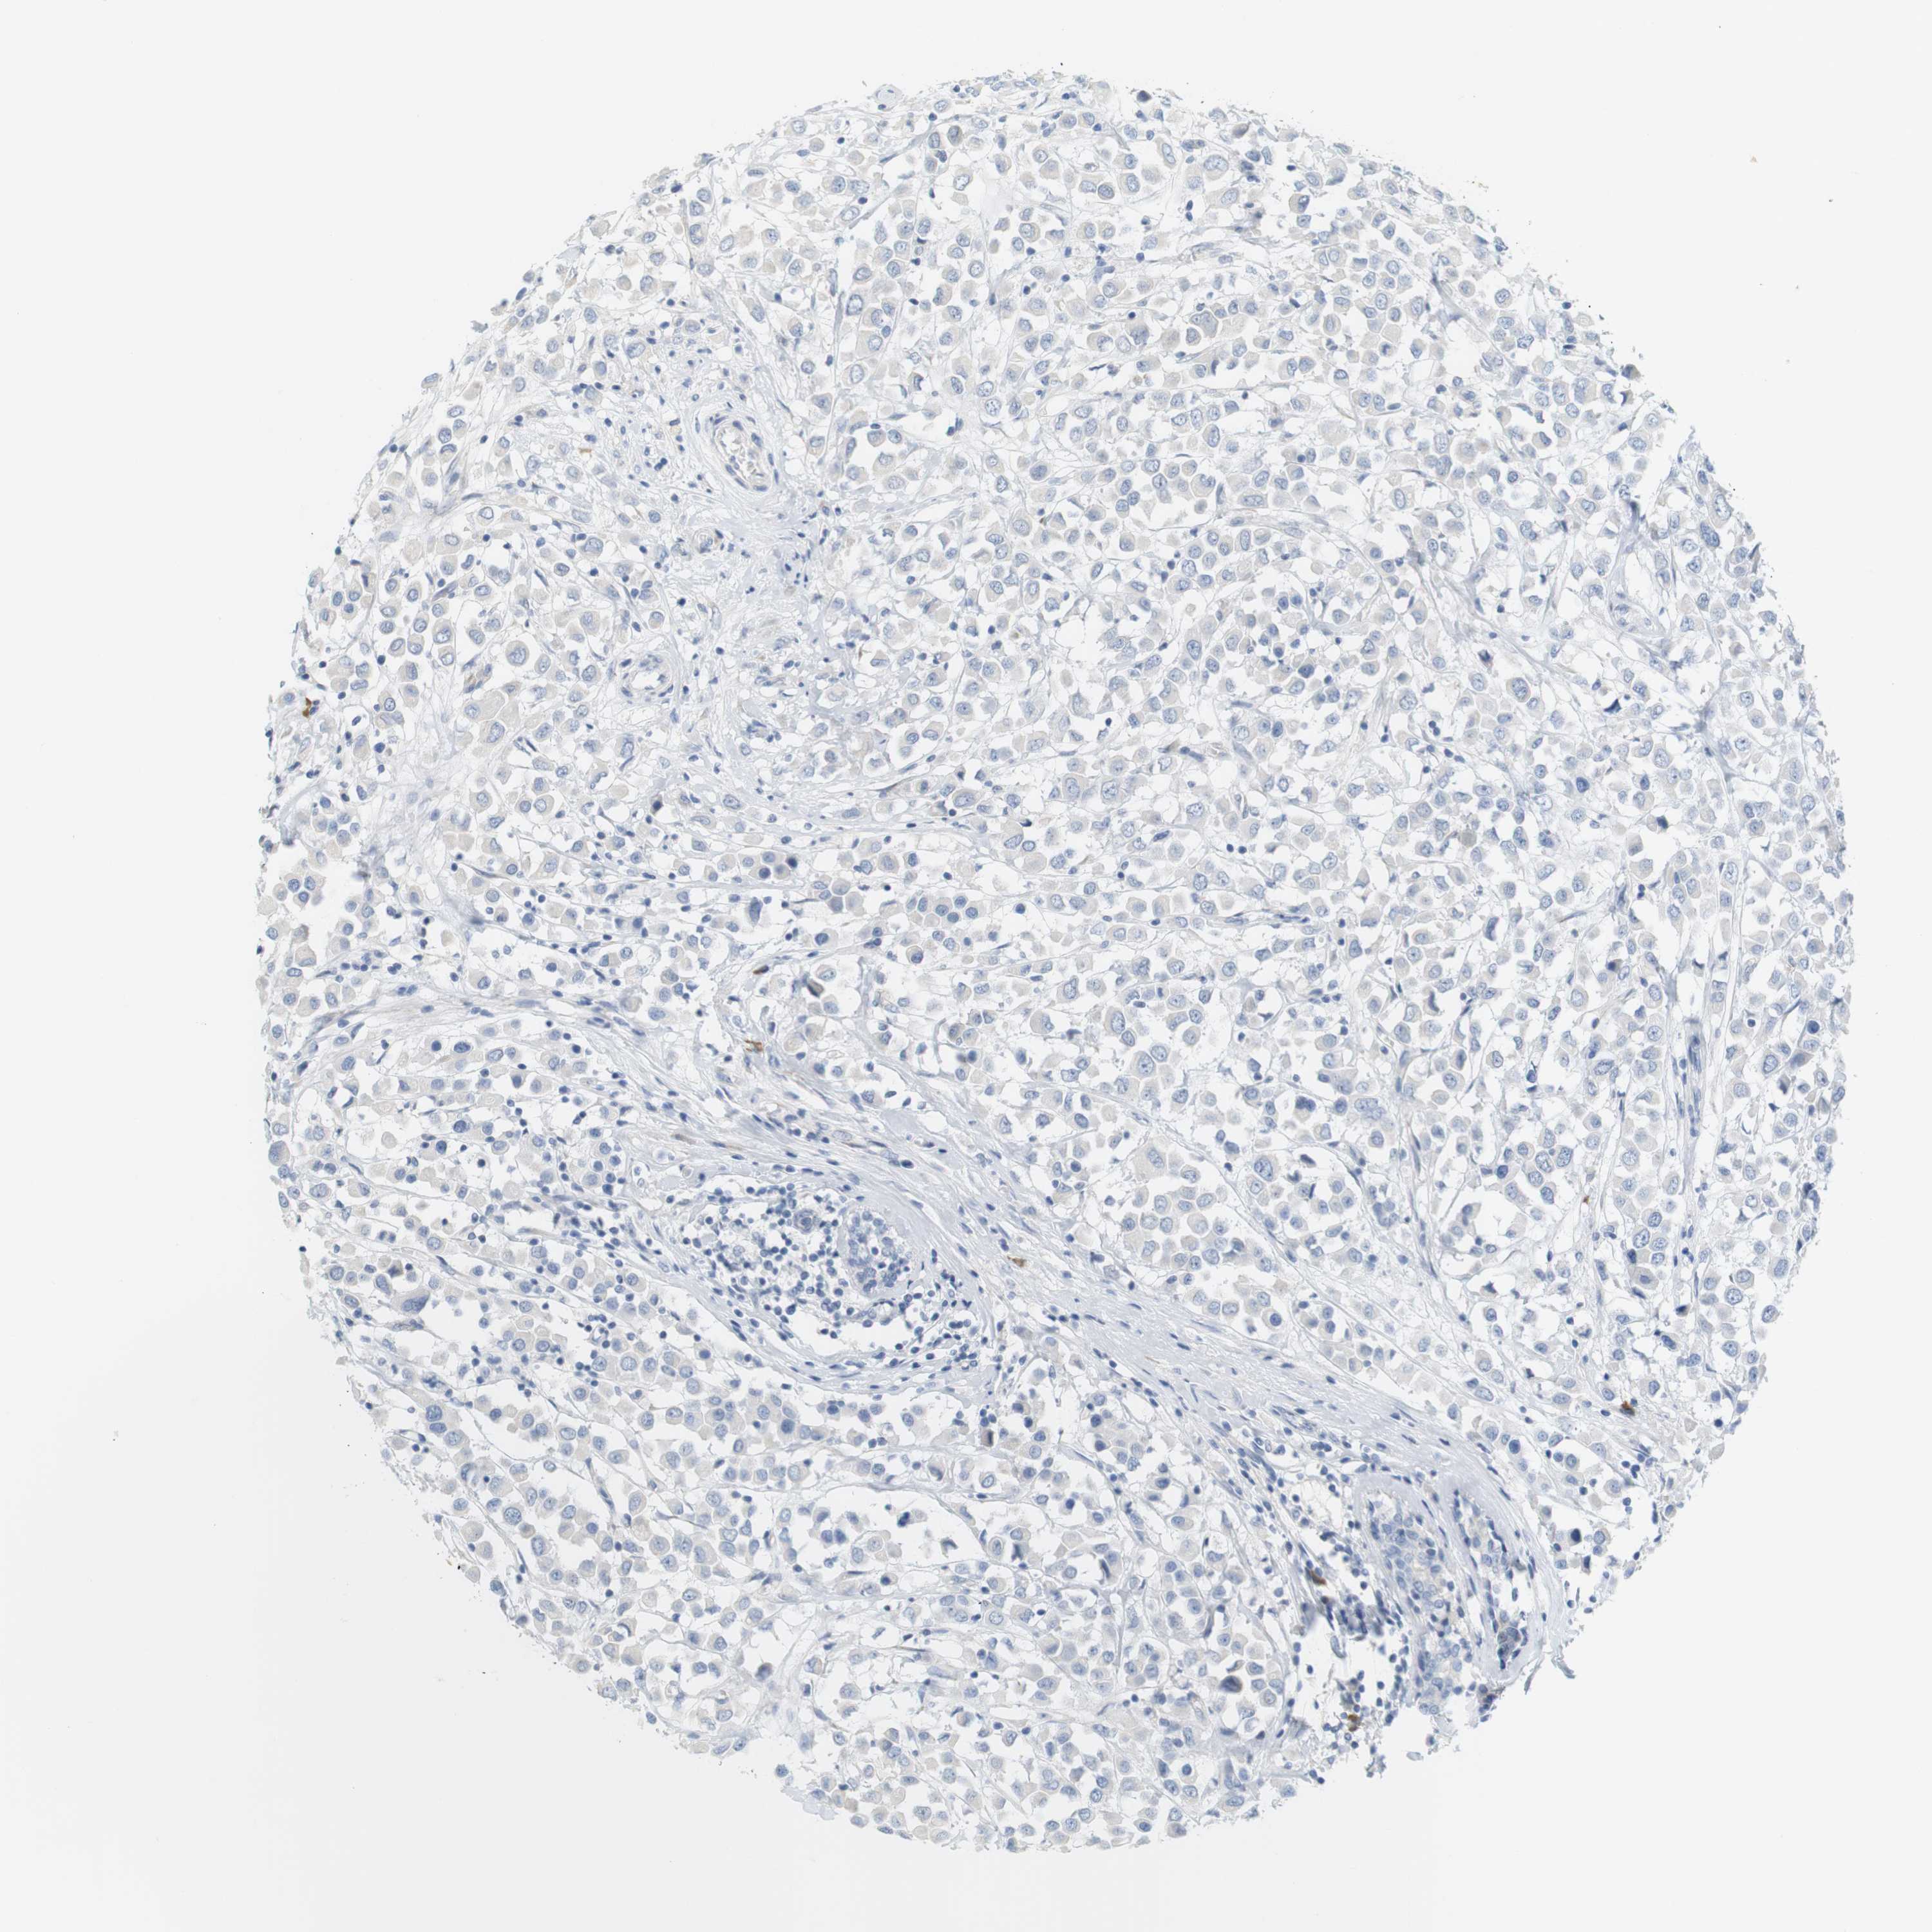

CANCER BREAST CANCER Show tissue menu

BRCA TCGA BRCA VALIDATION PROTEIN EXPRESSION

ANTIBODIES

AND

VALIDATION